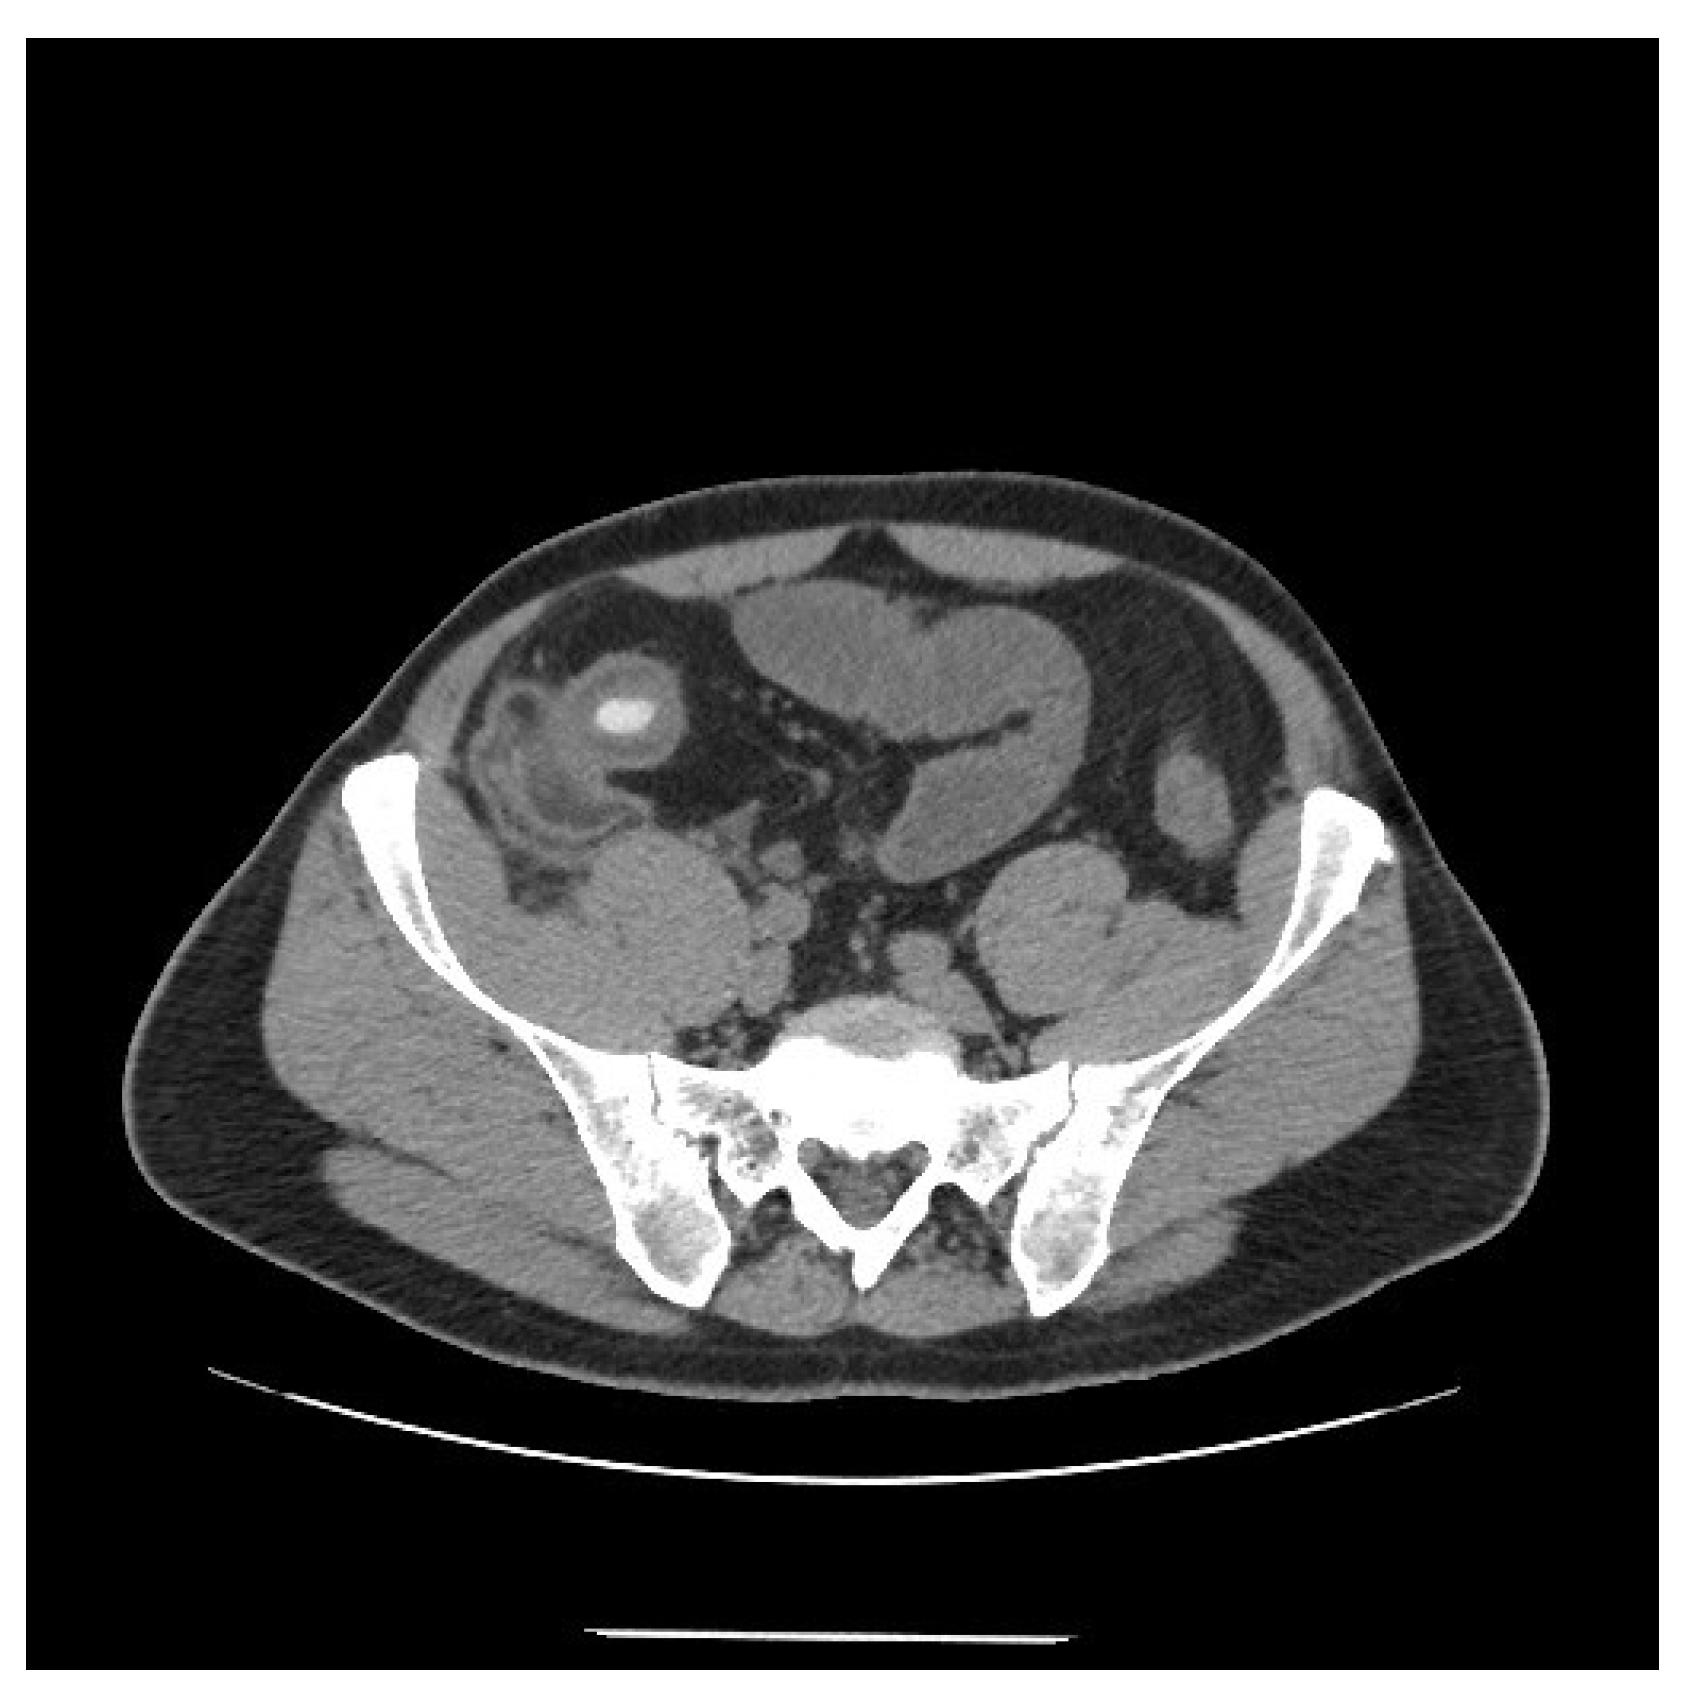

Figure 1.

Computed tomography scan showing thickening of the terminal ileum with a 14 mm intraluminal radiopaque mass.

On clinical examination, the abdomen was tender all over the quadrants, without any peritoneal signs elicited by manual palpation. Laboratory tests showed an increased white blood cell count of 12,000/mm3 and a C-reactive protein of 14.2 mg/dL. Computed tomography scan showed thickening of the terminal ileum with a 14 mm intraluminal radiopaque mass causing small bowel obstruction (Figure 1). Decision was taken to perform laparoscopic exploration of the abdomen for diagnostic and therapeutic purposes. During the laparoscopy, the thickened segment of small bowel was opened and a foreign body resembling a fruit pit was found within the inflamed lumen. The foreign body was extracted and closure of the small bowel was performed. Upon questioning the patient, after surgery, about the possibility of foreign body ingestion, it was discovered that the patient had accidentally swallowed a medlar pit a couple of days earlier. A month later a colonoscopy was performed, which confirmed a stenosis of the ileocecal valve suspicious for inflammatory bowel disease (Figure 2). Pathology examination of the biopsy specimens confirmed the diagnosis of CD involving the terminal ileum and the ileocecal valve. Due to the nature of the stenosis, which was fibrotic and stenotic, an ileocecal resection was planned and performed successively without any complications.